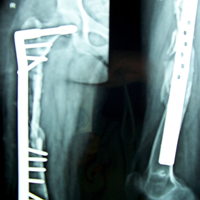

Case:5 Ewing sarcoma with implant failure

Orthopedic Oncology Doctor In Ahmedabad

Breakage of Nail

Sports Injuries Doctor

Refixation with Angle Bladed Plate and Sever Graft

Spine Best doctor

Ewing's Post Nailing and Bone Grafting

Best Trauma Surgeon in Ahmedbad

3 Months Post -Op

Joint Replacement

6 Months Post-Op